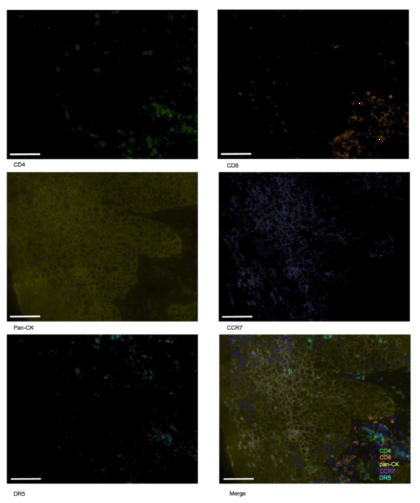

研究通过TissueGnostics的TissueFAXS平台(多光谱成像系统),对肿瘤组织样本进行多重免疫荧光染色与成像分析,核心目标是同时可视化并量化肿瘤微环境中关键免疫细胞及分子的分布与密度。

- 检测靶点覆盖:同步分析CD4+ T细胞、CD8+ T细胞、泛细胞角蛋白(pan-CK,标记肿瘤细胞)、CC趋化因子受体7(CCR7)、死亡受体5(DR5)等5种标志物,明确免疫细胞与肿瘤细胞的空间关系。

- 技术优势:通过光谱分离技术消除自发荧光干扰,*区分不同标志物的特异性信号,实现对复杂微环境中单一细胞群体的*计数与密度量化,为后续关联分析提供可靠数据基础。

TissueGnostics的StrataQuest软件用于图像数据分析,通过统一的阳性判定标准和密度计算方法,确保了35例纳入微环境分析的样本数据具有可比性和重复性;同时,该技术生成的可视化图像(如高/低响应组的免疫细胞分布对比图)也为研究结果提供了直观的形态学证据,增强了结论的可信度。

Figure 11 低应答患者中 CD4、CD8、泛细胞角蛋白、C-C 趋化因子受体 7 及死亡受体 5 的多重免疫荧光染色结果。